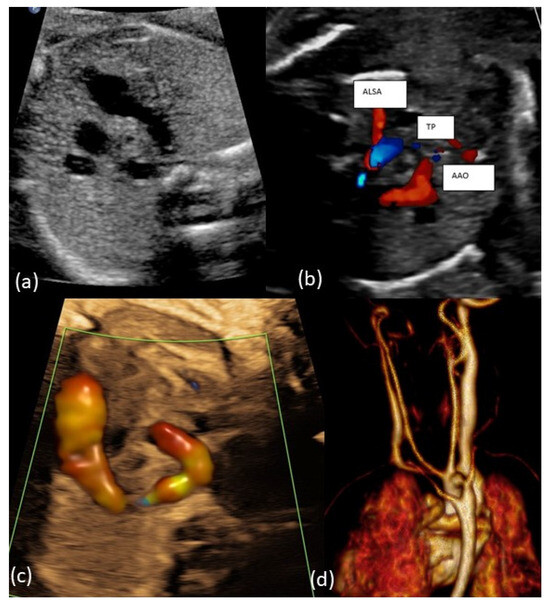

4.1. AAA Diagnostics of AAA and Accuracy Rate